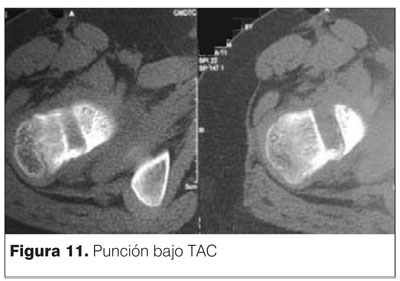

Se decide realizar procedimiento quirúrgico de resección mediante punción bajo tomografía axial computada (TAC). Se muestran las imágenes en las figuras 9, 10 y 11.

Se accede mediante un abordaje antero lateral de muslo y una punción antero posterior con trocar grueso (figura 12).